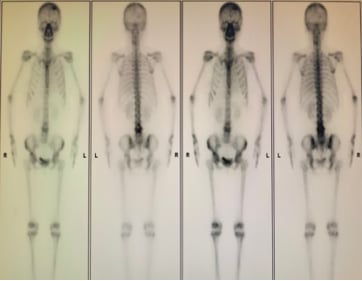

患者接受了规范的初始治疗:手术(左乳单切+SLNB+ALND),辅助化疗(AC-T*8周期),辅助放疗(患侧胸壁+锁骨上下区,50Gy/2Gy/25次),以及内分泌治疗(OFS+来曲唑)。2023年3月,为了强化治疗效果,医生为她加用了阿贝西利进行强化内分泌治疗。然而,尽管进行了积极治疗,疾病的进展依然迅速。2025年1月复查时疾病稳定,但仅两个月后,2025年3月强化内分泌治疗结束后,2025年4月复查就提示肺转移可能。胸部CT、骨扫描、头颅+腰椎CT等影像学检查均显示多发可疑病灶。最终,2025年5月的复查确诊为左乳癌术后肺、肝、左侧胸膜、骨转移,肝脏穿刺病理进一步证实为转移性腺癌,ER表达降至13%中+,PR阴性,HER2(2+),FISH阴性,再次确认HER2低表达。

骨转移的综合管理

对于存在多发骨转移,尤其是承重骨转移的患者,李颖医生强调了骨科会诊的重要性。及时评估是否需要提前进行干预,如放疗、手术或骨水泥注射等,以预防截瘫等严重并发症,对于提高患者的生活质量和延长生存期至关重要。